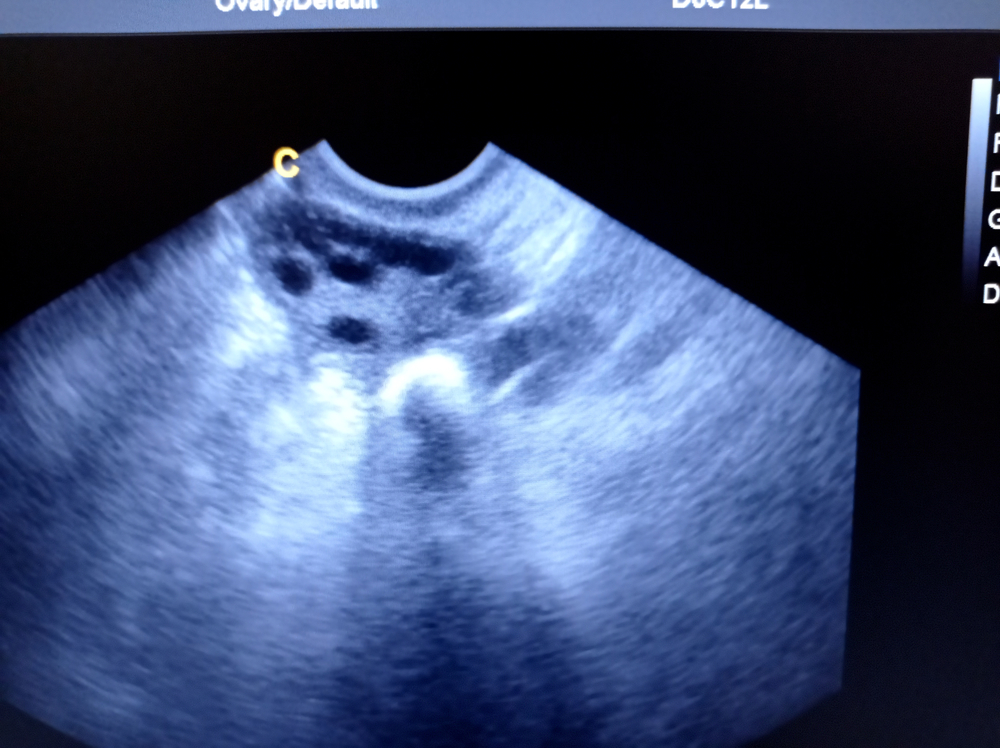

- фолликулы диаметром от 5 до 8 миллиметров, в середине цикла имеется доминантный фолликул диаметром 18–24 миллиметра;

УЗИ яичников показывает:

- поликистоз;

Что значит "фолликулы" в яичниках на УЗИ?

В норме во время ультразвукового исследования в яичниках присутствуют фолликулы. Они представляют собой структуры, в которых созревают яйцеклетки. Их наличие свидетельствует о том, что женщина способна зачать ребенка. Количество фолликулов влияет на шансы женщины забеременеть. Если есть 4–6 фолликулов, то риск зачатия низкий. Когда их количество от 7 до 12, процент зачатия высокий. Снижение фолликулов ниже 4 или увеличение более 16 подтверждает невозможность женщины забеременеть.